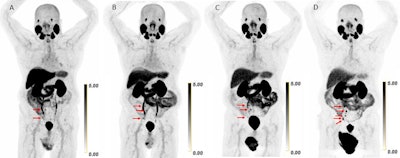

- What are Pluvicto discontinuation rates in a real-world setting?by Will Morton on January 5, 2026 at 8:27 am

There is a critical need to predict nonresponders and potential discontinuers prior to treatment.